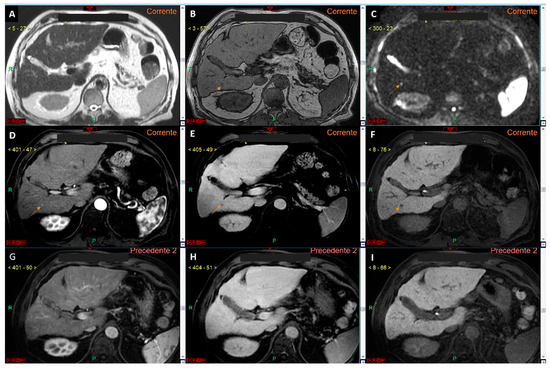

Figure 2.

T2-weighted image (A) and diffusion-weighted image with a b-value 0 (B). It is evident that the diffusion-weighted image (B) corresponds to the T2-weighted imaging (A) in terms of signal intensity, as demonstrated by the signal (hyperintensity) of the small cyst located in the liver segment IV.

Figure 3.

T2-weighted image (A), diffusion-weighted image with a b-value 0 (B), and diffusion-weighted image with a b-value 800 (C). The lesion located in the liver segment VI is clearly visible (arrows in (A–C)). It is evident that the conspicuity (hyperintensity) of the lesion is greater in the b-value 800 image (C). Moreover, the hyperintensity of the lesion in the b-value 0 image (B) is more pronounced compared to the T2-weighted image (A), confirming our hypothesis that the use of the b-value 0 could replace the T2-weighted sequence in aMRI protocols.